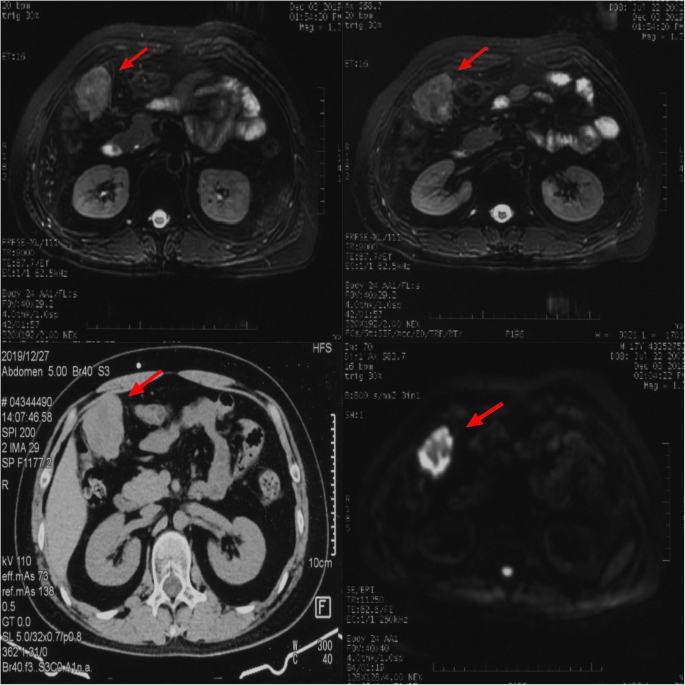

A 17-year-old Asian male presented with a long-standing history of generalized headache, diabetes insipidus, and intermittent fever without obvious inducement. An MRI examination (Fig. 2) revealed hydrocephalus due to space-occupying lesions, so the patient received a VP shunt to reduce HIP. Moreover, serum AFP tests were negative, but the β-HCG level in the cerebrospinal fluid reached 175.4 mIU/ml. Based on the imaging features and his symptoms, we speculated that this young man had iGCTs with intraventricular dissemination. Therefore, he received two cycles of a platinum-based regimen. Tests of the two blood tumor markers were negative, and MRI revealed 95% disappearance of the tumor after chemotherapy. Then, the patient completed irradiation of the whole central nervous system at a dose of 40 Gy/25 f. After 32 months of chemoradiation therapy, he reported intermittent abdominal pain without obvious inducement. Therefore, the abdomen of the young man was examined, and a mass in the right upper abdomen was discovered. Tests of the blood tumor markers were still negative, and MRI of the central nervous system showed no evidence of tumor recurrence (Fig. S1). However, rough-edged masses adjacent to the liver area were detected on abdominal MRI (Fig. 3). The patient then underwent a PET-CT examination, which showed multiple-site SUV elevation (12.1 to 13.6) in the abdominal cavity, so abdominal metastasis of GCTs was considered (Fig. 4 b1, b2). Therefore, urgent tumor resection was performed, and the returned pathological findings were consistent with metastatic iGCTs. IHC analysis of the abdominal lesion showed the following: AE1/AE3 (+), CD117 (+), Ki67 (70%), OCT3/4 (+), and sall-4 (+) (Fig. 5). After four courses of platinum-based chemotherapy, the patient was discharged and upgraded to a fair condition.

There were abnormal metabolic nodules near the inferior vena cava and the diaphragmatic apex, small nodules with slightly increased metabolism at the anterior right costal diaphragmatic angle, and extensive nodules with increased metabolism in the peritoneum (a) (marked in red and black arrows). Multiple-site SUV elevation in the abdominal cavity. The two main metabolic enhancement foci are concentrated in the right upper quadrant (b1, b2)